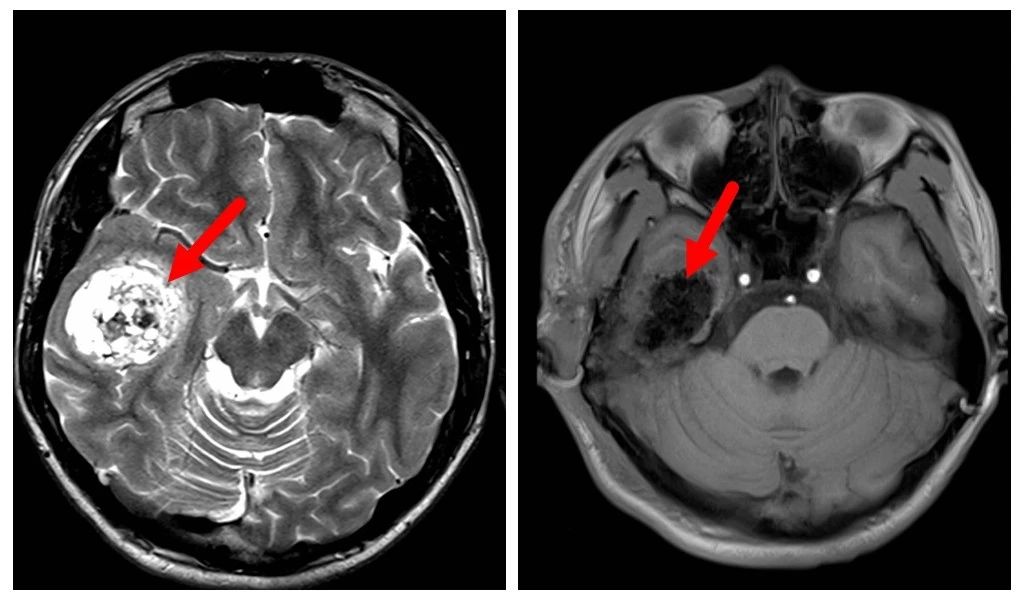

手術(shù)前后檢查對比

至此,讓小軍2年都無法展開笑顏的“罪魁禍?zhǔn)住苯K于被“擒住”,脫離他的軀體。目前,小軍正在積極的康復(fù)中。未來的生活依然美好,衷心祝愿小軍從此擺脫疾病困擾,重拾積極健康的心態(tài),擁抱幸??鞓返纳?!